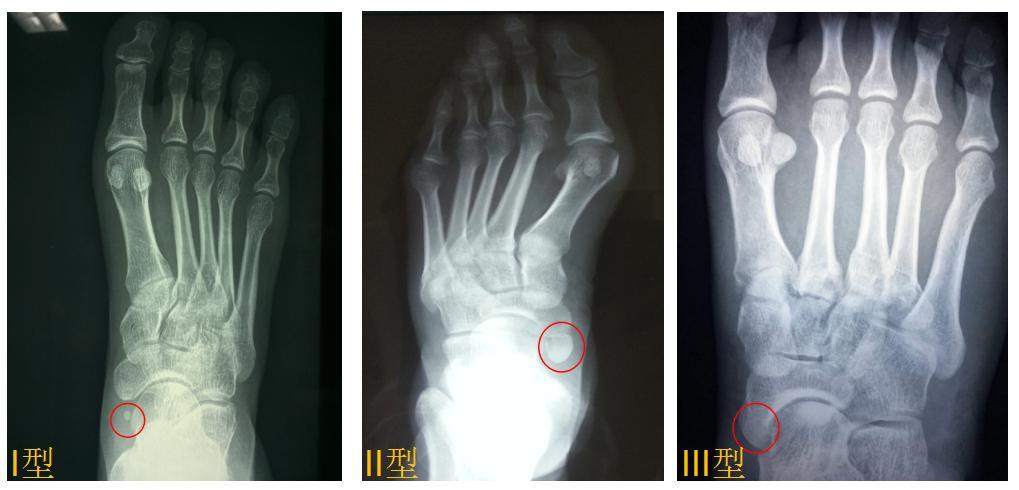

副足舟骨别忽略分型要牢记